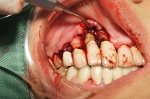

基本処置を施すも改善されなかったのでフラップ手術へ。

歯茎で覆い隠されていましたが中はかなり骨が吸収され歯石も大量に付着していました。

根の先まで歯石付着してしまっている歯